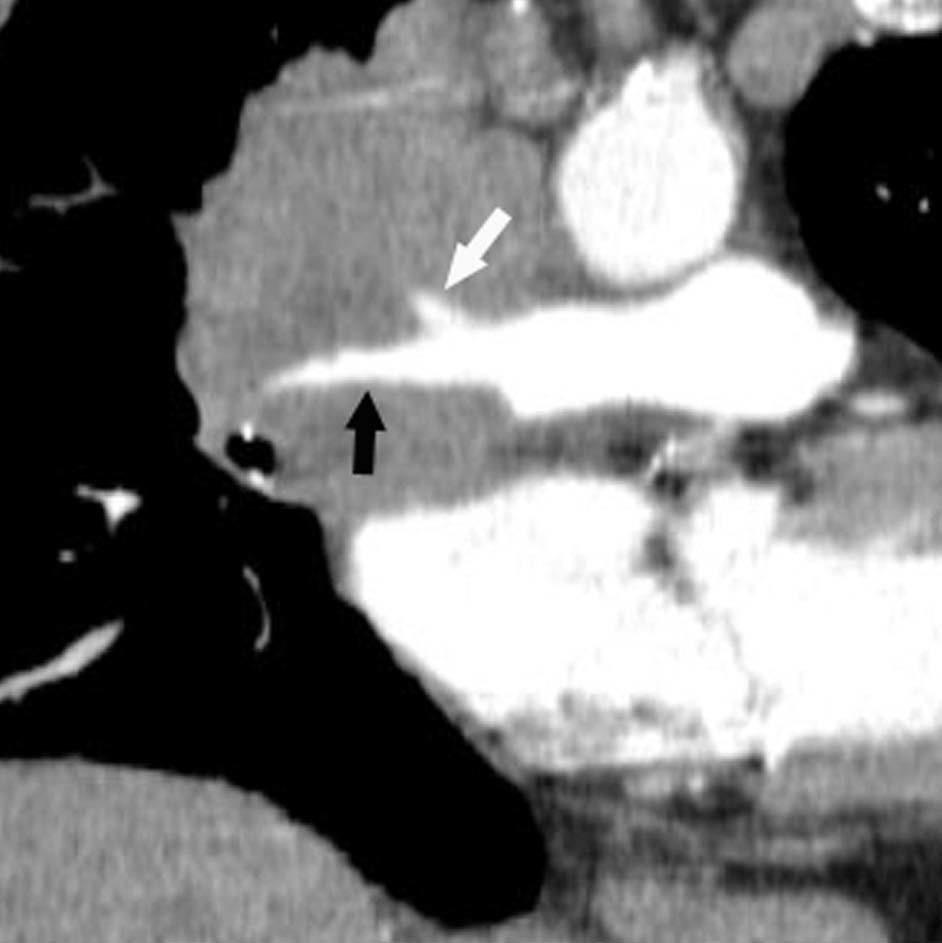

Pese a las conocidas limitaciones de la TC, ésta continúa siendo la técnica de elección en la estadificación del tumor en los pacientes con CPNM; su sensibilidad y especificidad en la determinación de la infiltración de pared oscilan entre el 38 y el 87% y del 40 al 90%, respectivamente, según las series. El desarrollo de nuevos equipos de TC helicoidal y principalmente las TC multidetectoras (TCMD) proporcionan unas imágenes 2D de mayor resolución con la posibilidad de hacer reconstrucciones multiplanares (MPR) en distintos planos del espacio e incluso 3D con la consiguiente mejora de la valoración del tumor, su extensión e infiltración de estructuras vecinas5 (fig. 4). Así, con la TCMD se puede poner de manifiesto con mayor fiabilidad la invasión de la cisura, la pared torácica o el mediastino, y además es capaz de determinar, gracias a las reconstrucciones de volumen, la relación exacta del tumor con la vía aérea (fig. 5). El progreso en la capacidad diagnóstica deriva del incremento en la resolución de las imágenes obtenidas y de la posibilidad de emplear nuevas aplicaciones como la broncoscopia virtual y la visualización en tiempo real. La broncoscopia virtual es útil para valorar la invasión del árbol traqueobronquial con la finalidad de planificar la cirugía, también como guía para el fibrobroncoscopista y, por último, porque permite ver el árbol bronquial distal a la estenosis (fig. 6)6. La capacidad de ver la imagen en tiempo real es especialmente útil cuando se emplea como guía en maniobras intervencionistas como biopsias percutáneas, ya sea con finalidad diagnóstica o como parte de la estadificación (fig. 7). Esta técnica de guía de biopsia denominada TC fluoroscopia reduce el número de pases y el tiempo global de la exploración, implica un menor riesgo de lesión de estructuras y permite la visualización inmediata de las posibles complicaciones7.

Fig. 4.--Invasión vascular. Tomografía computarizada (TC) torácica con contraste. Corte axial (A) y reconstrucción coronal oblicua (B). Invasión tumoral por continuidad de la vena pulmonar inferior (flecha).